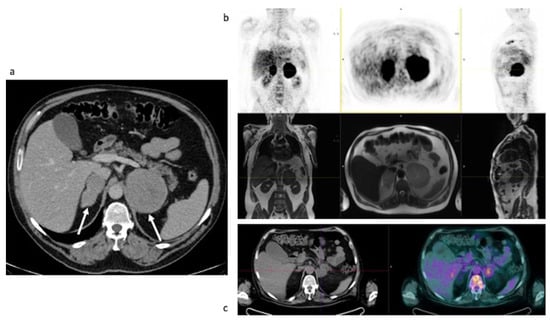

3.2.1. Initial Staging of Disease: Case #1